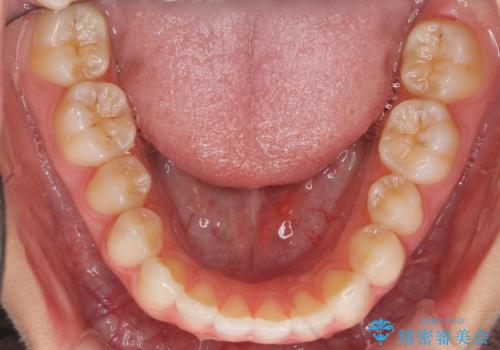

- 前歯の並びを主訴に来院。

前歯が出ており、また、左上の側切歯が1本生まれつき少ない状態でした。

また、右の奥歯の関係も上が前にある状態で大きくずれていました。

今回は左右とも1歯対2歯の関係であるため、それは変えずに前歯を可及的にひっこめて足りない部分をブリッジで補う治療としました。

奥歯の関係を完全に1級にするには右上の小臼歯の抜歯が必要でしたが、もともと左上の前歯が生まれつき少ないため今回は歯を抜かずに治療しています。